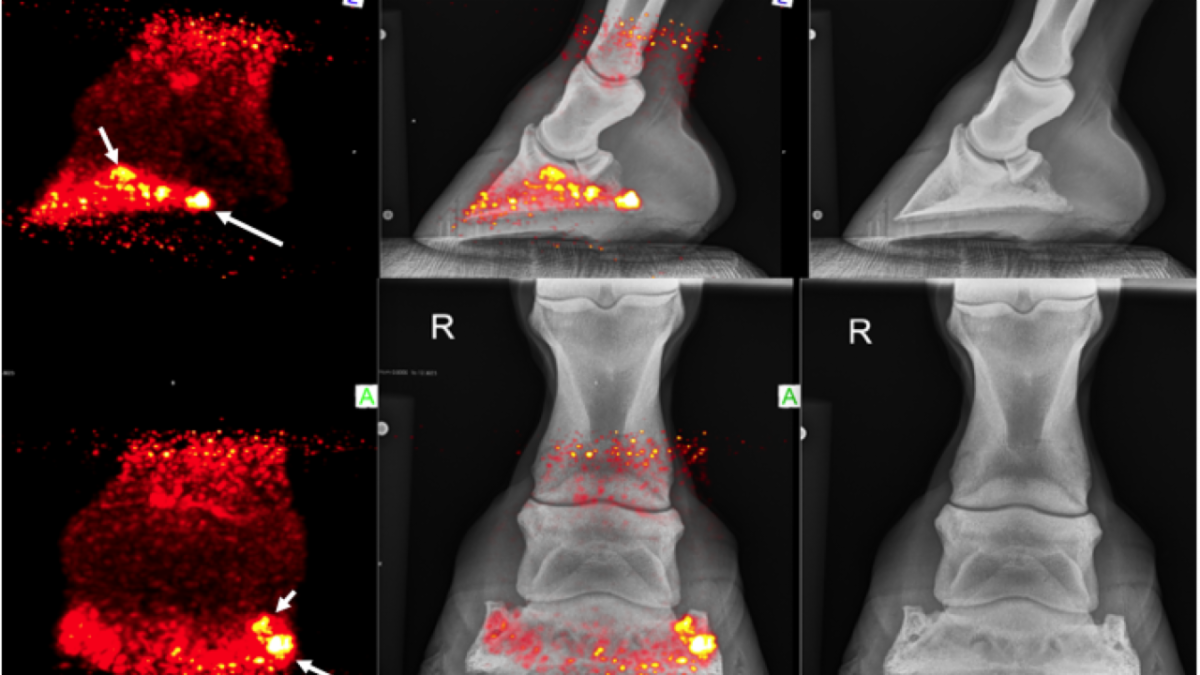

Success of UC Davis Equine PET Scan Research on Racehorses Translates to Clinical Breakthroughs for Sport and Pleasure Horses

Standing equine positron emission tomography (PET) imaging is not just for racehorses anymore. In the first four months since the installation of the MILEPET scanner at the UC Davis veterinary hospital, 100 horses have been imaged; more than half were performance and pleasure horses.

On August 5, UC Davis veterinary radiologist Dr. Mathieu Spriet presented "New Equine Imaging Options with Standing PET at UC Davis," an informative webinar to update veterinarians on the latest in positron emission tomography (PET) for horses. Full webinar available for viewing.